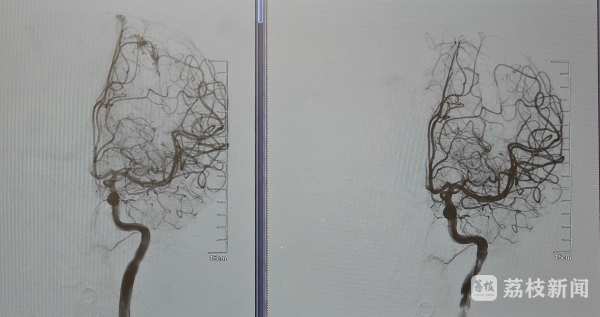

手术由神经外科邱德智带领的脑血管病团队实施。邱德智医生表示:“从头颅CT检查,很难明确出血病因及出血部位,如果直接开颅找出血点止血,脑组织损伤比较大,风险非常高。”因此,术中首先采用介入,由大腿股动脉将导管探至颅内血管,打入造影剂,通过显影准确找到了出血的病因:脑动静脉畸形,也印证了术前的判断。

“畸形血管团位于脑功能区,开颅切除畸形血管团可能会进一步损伤脑组织,加重患儿症状。”邱德智医生决定采用血管内栓塞治疗动静脉畸形,术中将细如头发丝的微导管超选至畸形团的供血动脉处,缓慢注入液态栓塞剂,使其向畸形团内弥散,防止栓塞剂返流。最终治愈性栓塞动静脉畸形,栓塞完成,出血便止住了。邱德智和张献礼也终于松了口气,下一步就是清除脑血肿。